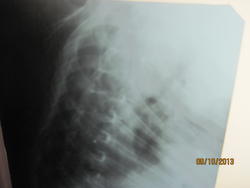

УЗИ плевральных полостей - жидкости нет.

9.10.13g_pryahin_kontrol.jpg

И средостение на месте.